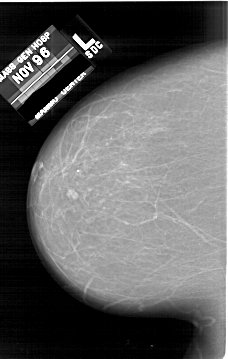

A_1623_1.LEFT_MLO

LEFT_MLO LINES 6601 PIXELS_PER_LINE 4426 BITS_PER_PIXEL 12 RESOLUTION 43.5 NON_OVERLAY